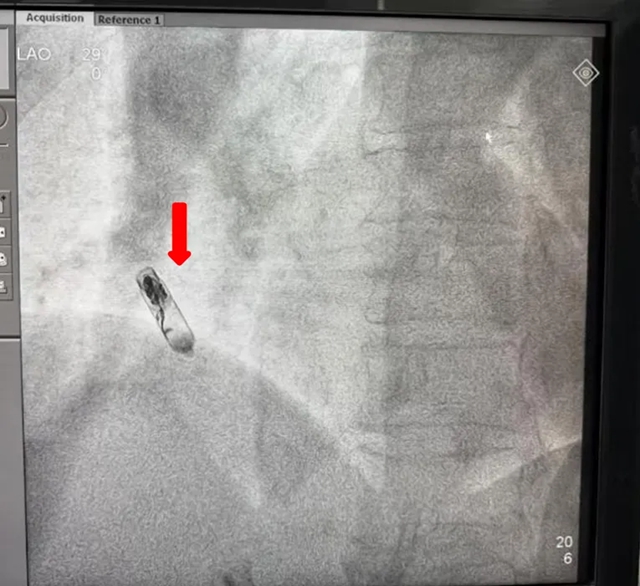

螺旋锚定:通过DSA影像引导,将起搏器的双螺旋电极精准旋入右心耳基底部,多角度X线透视确认位置稳固;

植入后

注:红色箭头为无导线起搏器,黄色为递送系统

术中影像